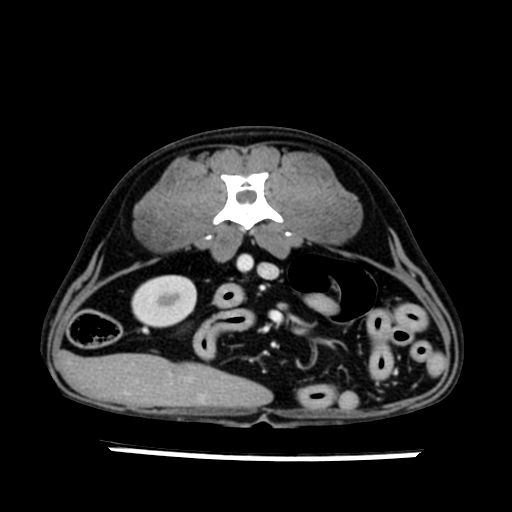

prescritto esame TAC

sequenza immagini limitata al fegato reni e surreni

le immagini ecografiche rispetto alla tac datano circa 7 mesi prima ,le surrenali sono normali nonostante il test acth sia risultato positivo .all’esame TAC dopo diversi mesi risultano aumentate armonicamente nel volume e si individua un forte sospetto di adenoma ipofisario .

sospetto adenoma ipofisario vs. meno probabilmente meningioma della base; intertiziopatia polmonare; lesione espansiva epatica, verosimilmente del lobo laterale sinistro, di sospetta natura neoplastica; lesioni spleniche di natura da definire; iperplasia/ipertrofia delle ghiandole surrenali, bilateralmente; vertebra di transizione del rachide toracico; tenosinovite cronica del muscolo bicipite brachiale di destra.

- Nessuna informazione diversa per quello che riguarda l’esame ecografico del fegato e la presa del contrasto si confermano le lesioni individuate e l’ipoenanchement in fase portale.

- la total body permette di escludere metastasi e di avvicinarsi all’interventistica